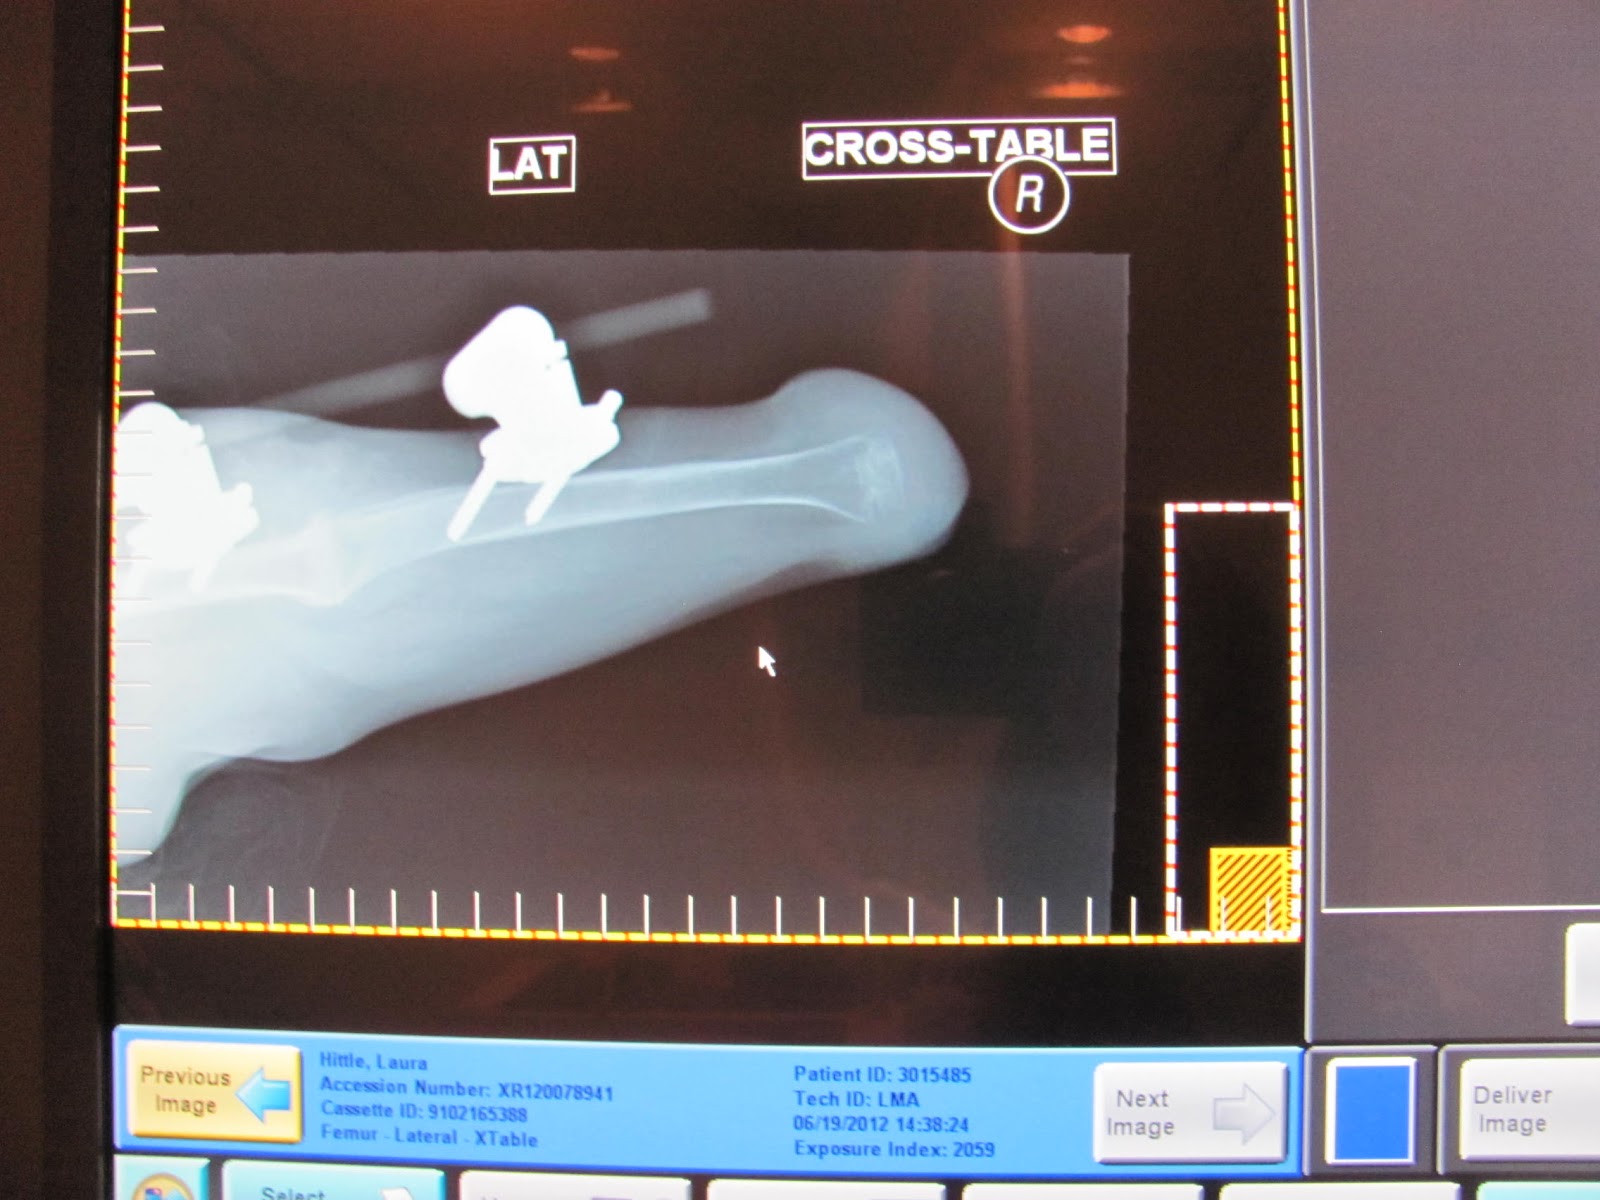

Here's a close up of our torture contraption! Lol! Laura hated pin cleaning!! We had to unbandage and clean the pins twice a day. Laura screamed bloody murder each and every single time. The scar is where her knee used to be. This makes more sense when you see the X-rays below.